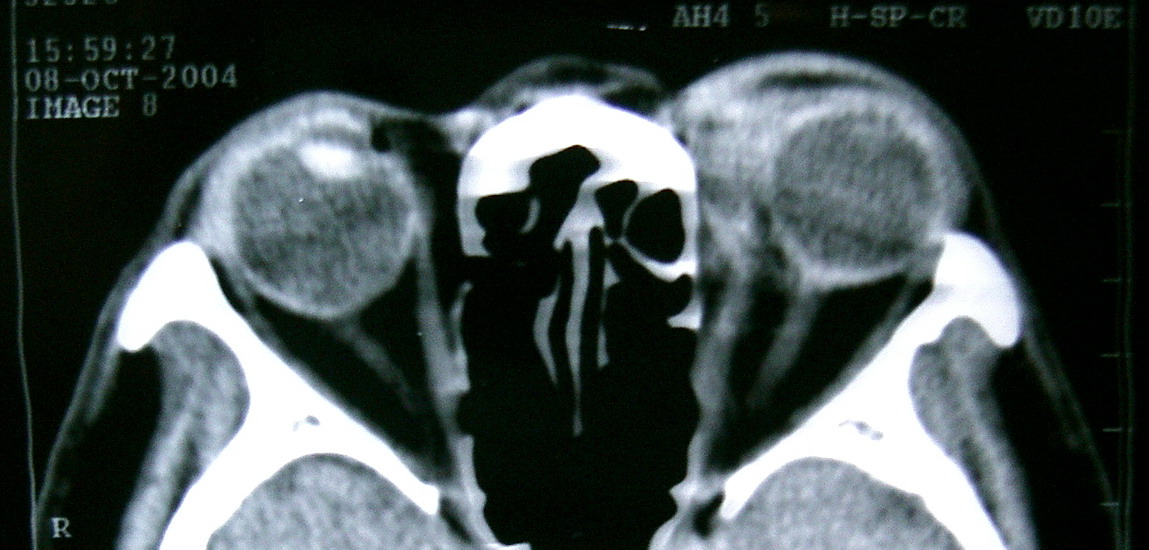

眼眶冠扫,平扫CT: 左眼球内上方可见不规则软组织块影,大小约2.5*1.0CM,与邻近组织分界不清,相邻之内直肌、上直肌增粗,眼环正常,眶壁骨质无破坏,左上颌窦底部可见粘膜增厚,其余副鼻窦未见异常。 IMP:1,左眼眶肿物;2,左上颌窦炎